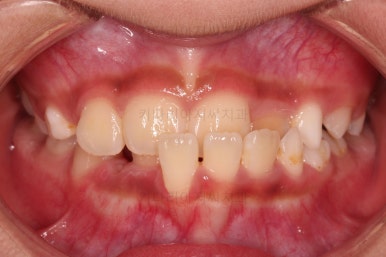

무려 4개월 만에 부산어린이교정 치료가 종료되었습니다.

앞니의 교합이 매우 안정적이여서 치료를 끝냈고요.

전후 비교해 보겠습니다.

반대교합이 완벽히 개선되면서 주걱턱으로 보였던 얼굴형태도 완벽히 개선되었고요.

한 쪽으로 치우치던 아래턱의 위치도 돌아오면서 비대칭이 개선되었습니다.

심지어는 위아래 앞니가 삐뚤었던 부분도 일정 부분 좋아졌습니다.

반대교합으로 인해 아래 앞니 잇몸 퇴축이 있었던 부분은 되돌아오지는 않는 점이 아쉽습니다.